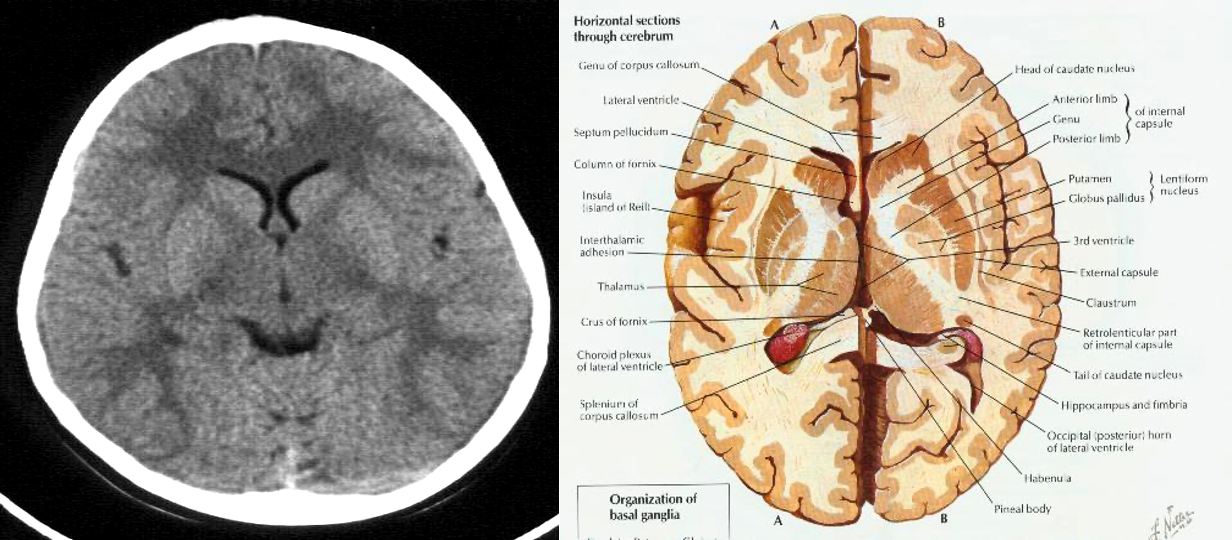

Ventricular anatomy

CT show the anatomy of skull in transverse section